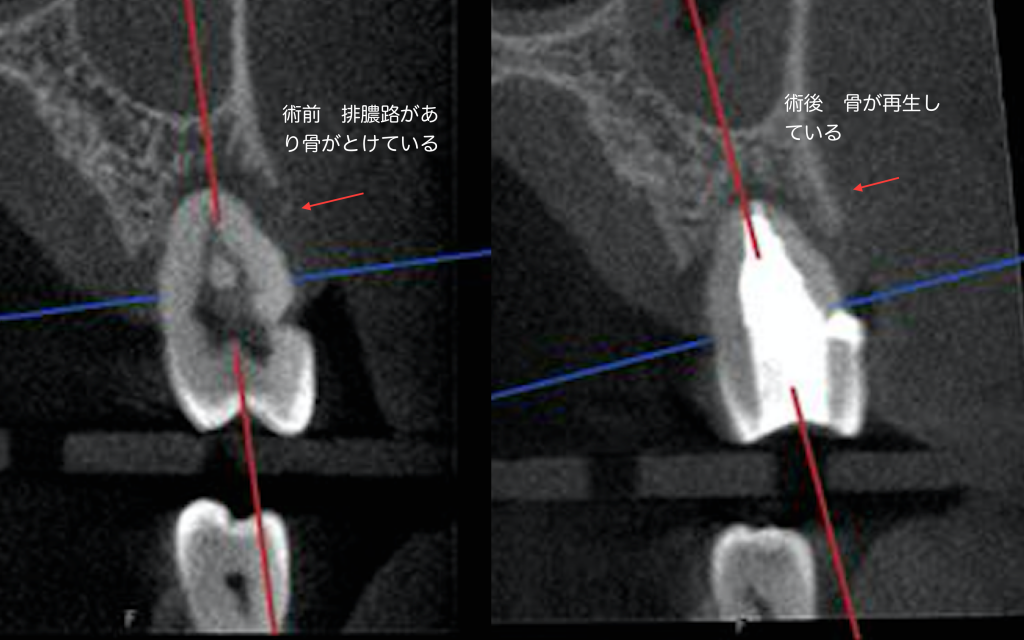

根管治療により排膿路が消えたNo2

こちらの患者様は歯頚部に力により欠損が出来てそこから歯の内部に細菌感染がおこり歯髄がダメージを受け根先端が化膿して排膿を起こして歯周ポケットのような排膿路が出来た症例です。

2.5ヶ月にCTを撮影して治癒を確認致しました。骨が見事に再生していることに注目して下さい。

根管治療が成功した結果、排膿路が消え歯周ポケットがなくなりました。